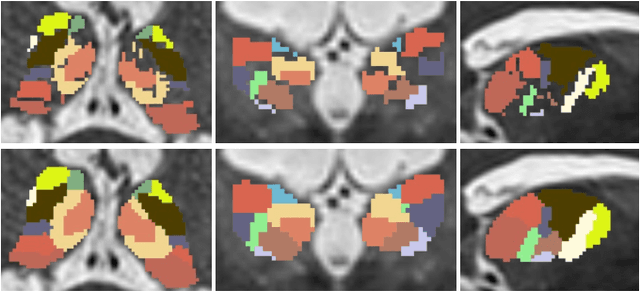

Abstract:Data-driven thalamic nuclei parcellation depends on high-quality manual annotations. However, the small size and low contrast changes among thalamic nuclei, yield annotations that are often incomplete, noisy, or ambiguously labelled. To train a robust thalamic nuclei parcellation model with noisy annotations, we propose a label propagation algorithm based on random walker to refine the annotations before model training. A two-step model was trained to generate first the whole thalamus and then the nuclei masks. We conducted experiments on a mild traumatic brain injury~(mTBI) dataset with noisy thalamic nuclei annotations. Our model outperforms current state-of-the-art thalamic nuclei parcellations by a clear margin. We believe our method can also facilitate the training of other parcellation models with noisy labels.

Abstract:The thalamus is a subcortical gray matter structure that plays a key role in relaying sensory and motor signals within the brain. Its nuclei can atrophy or otherwise be affected by neurological disease and injuries including mild traumatic brain injury. Segmenting both the thalamus and its nuclei is challenging because of the relatively low contrast within and around the thalamus in conventional magnetic resonance (MR) images. This paper explores imaging features to determine key tissue signatures that naturally cluster, from which we can parcellate thalamic nuclei. Tissue contrasts include T1-weighted and T2-weighted images, MR diffusion measurements including FA, mean diffusivity, Knutsson coefficients that represent fiber orientation, and synthetic multi-TI images derived from FGATIR and T1-weighted images. After registration of these contrasts and isolation of the thalamus, we use the uniform manifold approximation and projection (UMAP) method for dimensionality reduction to produce a low-dimensional representation of the data within the thalamus. Manual labeling of the thalamus provides labels for our UMAP embedding from which k nearest neighbors can be used to label new unseen voxels in that same UMAP embedding. N -fold cross-validation of the method reveals comparable performance to state-of-the-art methods for thalamic parcellation.